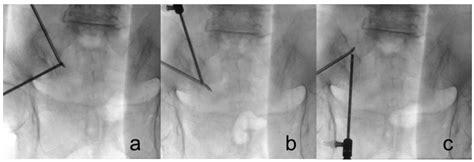

Biportal Endoscopic Radiofrequency Ablation of the Sacroiliac Joint ...

mdpi.com